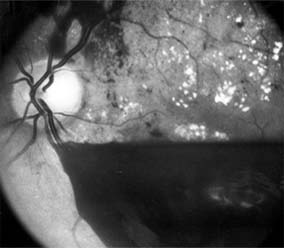

Diabetic retinopathy is a progressive microangiopathy characterized by small vessel damage and occlusion. The earliest pathologic changes are thickening of the capillary endothelial basement membrane and reduction of the number of pericytes. Background diabetic retinopathy is a clinical reflection of the hyperpermeability and incompetence of involved vessels. The capillaries develop tiny dot-like outpouchings called microaneurysms, while the retinal veins become dilated and tortuous (Figure 10-20).

Figure 10-20

Figure 10-20: Background diabetic retinopathy with abundant macular exudate (open arrow), micro-aneurysms (small arrow), and intraretinal hemorrhage (large arrow).